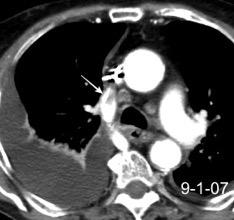

Síndrome de afectación postcardiaca (postcardiac injury)

Post infarto 1-7 % (Dressler)

Trauma cerrado Implantación marcapasos

Cirugía cardiaca. 17-31% (Post.pericardiotomía)

3707 pacientes 29 Derrames (0,78%) > de 25% del hemitórax

Todas menos 2 Izdos.

Angioplastia

By-pass coronario 21-10-03